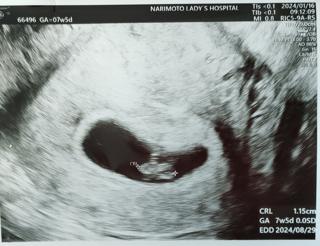

写真:7w5d:桃さん

ちょうど6w0dの頃から続く出血…最初は鮮血で3日ほど経って黒っぽいものに…現在も生理最終日くらいの茶色い出血が続いてて、半ば諦め気味に受診。

大きさも心拍も問題なく成長できてました…(´;ω;`)

CRL11.5mm

4人目になる子なので上(7歳、3歳半、1歳半で全員男の子)の世話で出血してようが身体を気遣うことも出来ず申し訳ないけど…強く育って元気に産まれてきてほしいです!